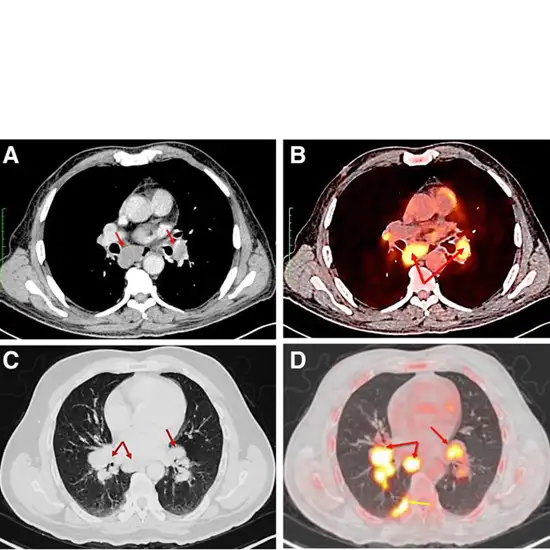

CECT (Contrast Enhanced Computed Tomography) Axilla is a non-invasive imaging scan that creates pictures of the Axilla (Armpit). This scan is to diagnose the lymph nodes at the armpit and the axillary lymph nodes in patients with breast cancer. To perform this scan, contrast media is given to the patient, and an x-ray beam is used.